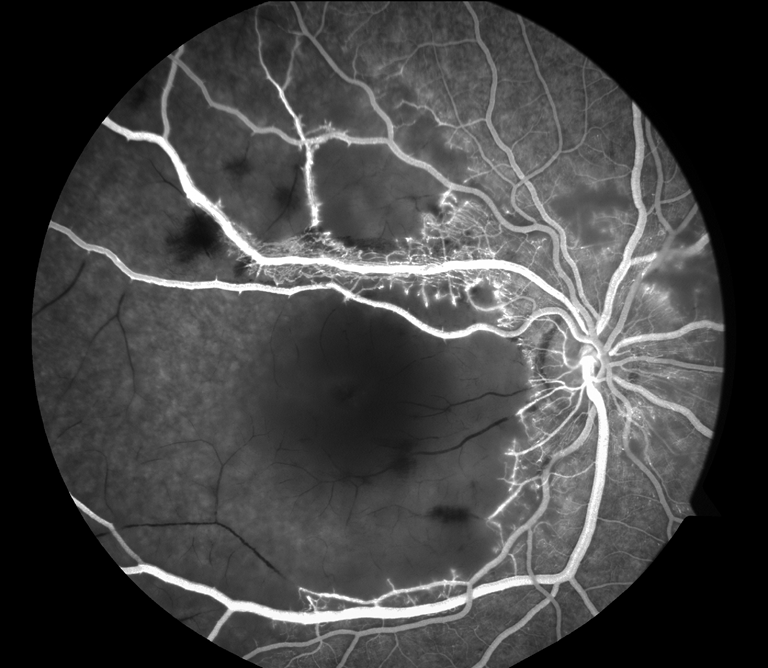

Vascular Occlusive Disease

Presented by James Gilman, BSc, CRAThis photograph received Honorable Mention in the category "Retinal Fluorescein Angiography" and was displayed at the 2024 ASCRS/OPS Society Exhibit.